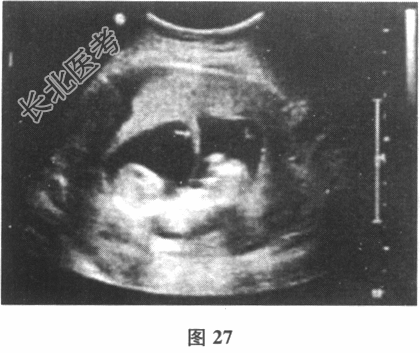

- [材料题] 35岁女性,G1P0,因原发不孕辅助生殖受孕,移植两枚囊胚均存活。移植后6周超声提示宫腔内两个孕囊,每个孕囊均可见一个胎芽伴胎心搏动。停经13周查超声如图27所示。